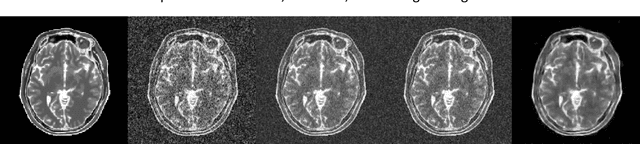

Abstract:In this paper, we propose a method for denoising diffusion-weighted images (DWI) of the brain using a convolutional neural network trained on realistic, synthetic MR data. We compare our results to averaging of repeated scans, a widespread method used in clinics to improve signal-to-noise ratio of MR images. To obtain training data for transfer learning, we model, in a data-driven fashion, the effects of echo-planar imaging (EPI): Nyquist ghosting and ramp sampling. We introduce these effects to the digital phantom of brain anatomy (BrainWeb). Instead of simulating pseudo-random noise with a defined probability distribution, we perform noise scans with a brain-DWI-designed protocol to obtain realistic noise maps. We combine them with the simulated, noise-free EPI images. We also measure the Point Spread Function in a DW image of an AJR-approved geometrical phantom and inter-scan movement in a brain scan of a healthy volunteer. Their influence on image denoising and averaging of repeated images is investigated at different signal-to-noise ratio levels. Denoising performance is evaluated quantitatively using the simulated EPI images and qualitatively in real EPI DWI of the brain. We show that the application of our method allows for a significant reduction in scan time by lowering the number of repeated scans. Visual comparisons made in the acquired brain images indicate that the denoised single-repetition images are less noisy than multi-repetition averaged images. We also analyse the convolutional neural network denoiser and point out the challenges accompanying this denoising method.